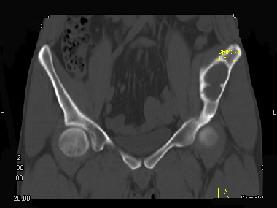

问题 男,34岁,左髂骨疼痛,有皮肤色素沉着,性早熟等,请结合所提供图像,选择最佳答案 ( )

选项 A、内生软骨瘤 B、骨巨细胞瘤 C、畸形性骨炎 D、骨纤维结构不良 E、非骨化性纤维瘤

答案 D